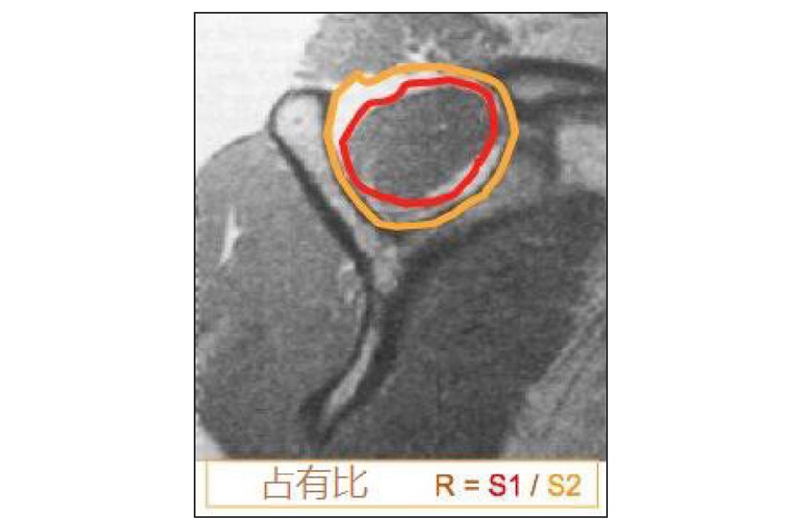

尽管该方法缺乏一致性,但常用于评估肩袖肌肉脂肪浸润情况。Fuchs等根据CT和MRI影像也发表了一个类似的分型。Thomazeau等根据肩关节 MRI 斜矢状位T1像中冈上肌肌腹在冈上窝所的占有比例进行分度(图7),其中:

I级为正常或轻微萎缩,占有比为1.0~0.6;

II级为中度萎缩,占有比为0.6~0.4 ;

III级为严重萎缩,占有比<0.4。

图7 冈上肌肌腹在冈上窝内的占有比

注:S1为冈上肌肌腹的横截面;S2为冈上窝的横截面;R=S1/S2